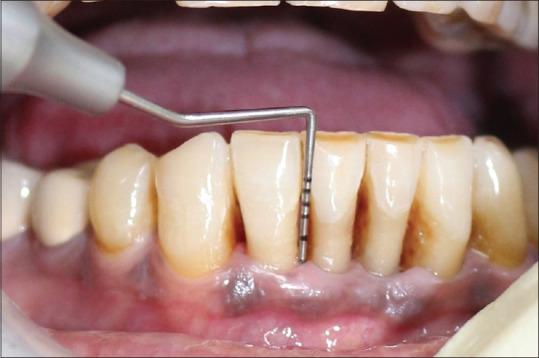

A total of 16 known cases of chronic Periodontitis patients who were suffering from type 2 DM were allocated into two groups. The test group ( = 8) was treated with standard scaling and root planing (SRP) along with PDT while the control group was treated with SRP alone. Various clinical parameters assessed were plaque index, gingival index, pocket probing depth, clinical attachment level, and Glycated hemoglobin level at baseline and 90 days after therapy.

将1共6例已知患有2型糖尿病的慢性牙周炎患者分为两组。试验组( = 8)接受标准龈上洁治和根面平整(SRP)联合PDT治疗,而对照组仅接受SRP治疗。评估的各种临床参数包括基线时以及治疗后90天的菌斑指数、牙龈指数、牙周袋探诊深度、临床附着水平和糖化血红蛋白水平。